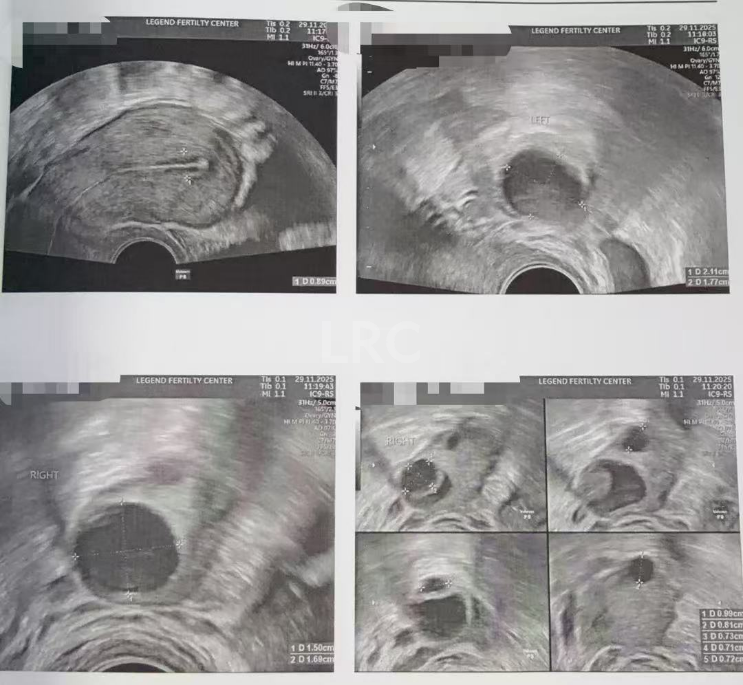

月经第二天 促排第一天

阴超检查:基础卵泡 6 颗

-右侧 3 颗 (4,3,3mm)

-左侧 3 颗 (5,4,3mm)

促排第四天

阴超检查(只数能用卵子):

- 右侧可用卵泡 1 颗(9mm)

- 左侧可用卵泡 1 颗 (10mm)

促排第六天

阴超检查:

- 右侧卵泡 1 颗可用 (11,6mm)

- 左侧卵泡 1 颗 (13mm)

促排第九天

- 右侧卵泡 1 颗可用 (17,8,8,7,5mm)

- 左侧卵泡 1 颗 (19mm)